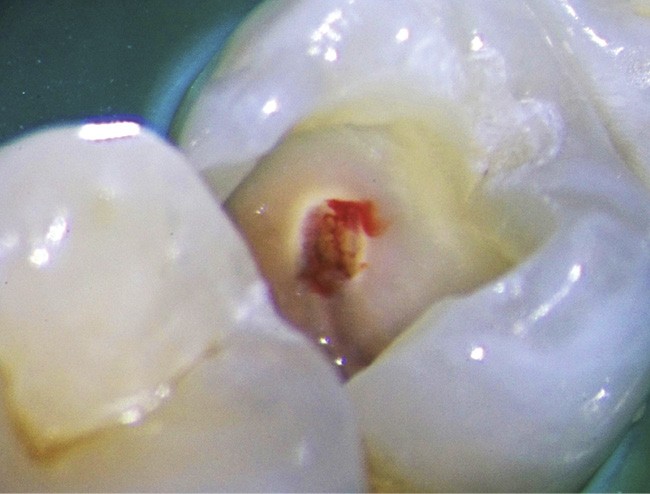

Coiffages pulpaires

L’exposition pulpaire a deux causes principales : traumatique ou carieuse.

Dans le cas d’un traumatisme récent, chez le jeune ou l’adulte, la pulpe doit être systématiquement coiffée pour conserver la vitalité pulpaire

Concernant les coiffages sur dents adultes, un bon diagnostic doit être posé pour faire le bon choix entre la conservation pulpaire totale, partielle ou le traitement endodontique [34]. Il est particulièrement indiqué chez le jeune dont les dents immatures ont une édification apicale incomplète.

Plusieurs facteurs interviennent dans le bon pronostic du coiffage pulpaire : l’élimination de l’inflammation, le contrôle de l’infection et la biocompatibilité des matériaux utilisés [35].

Le laser Er:YAG va permettre une élimination des débris en surface, une stérilisation, avec comme irrigation de l’eau stérile [36] et en coupant le spray, une hémostase avec la formation d’une couche de coagulation [37] propre à la formation d’un pont dentinaire au contact du biomatériau, qui peut être bio-actif, tel que la Biodentine (Septodont) (fig. 6a à d).

Protocole opératoire : sous anesthésie, une cavité suffisante à recevoir le biomatériau (2 à 3 mm) sous champ opératoire est réalisée. La désinfection au laser Er:YAG (40 mJ ; 20 Hz) sous spray, pendant 20 secondes, est alors mise en œuvre. S’en suit éventuellement une coagulation de 3 secondes, en coupant le spray, puis la mise en place du biomatériau Biodentine (Septodont). Il sera ensuite recouvert d’un matériau de restauration adéquate.